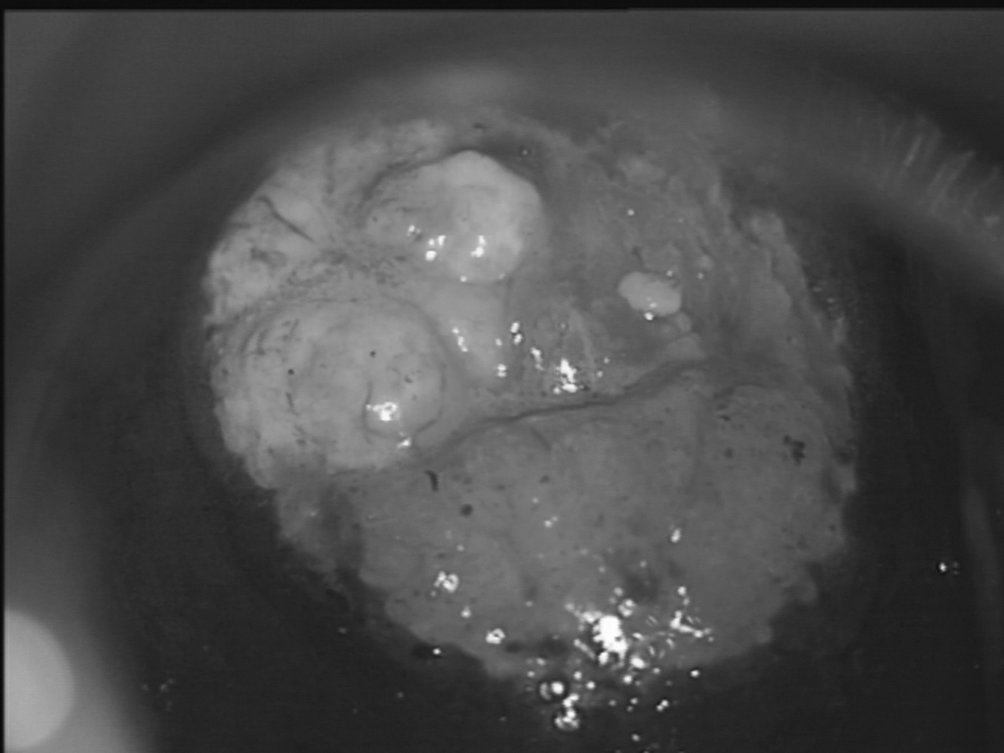

Figure 18.7 Zone acidophile cervicale antérieure correspondant à une CIN 3 à la biopsie

Figure 18.7 Zone acidophile cervicale antérieure correspondant à une CIN 3 à la biopsie.